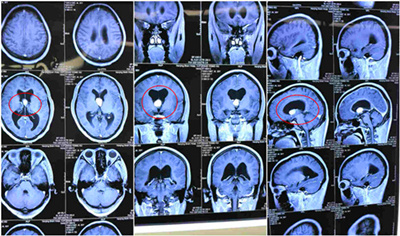

術(shù)前CT影像資料:不同截面,紅圈內(nèi)白色物體為腫瘤物